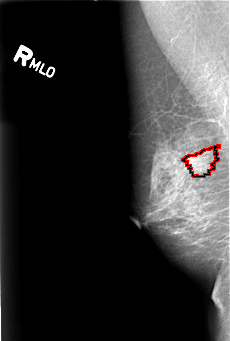

B_3016_1.RIGHT_MLO

RIGHT_MLO LINES 4424 PIXELS_PER_LINE 2984 BITS_PER_PIXEL 12 RESOLUTION 50 OVERLAY

FILE: B_3016_1.RIGHT_MLO.OVERLAY

TOTAL_ABNORMALITIES 1

ABNORMALITY 1

LESION_TYPE MASS SHAPE IRREGULAR MARGINS SPICULATED

ASSESSMENT 4

SUBTLETY 3

PATHOLOGY MALIGNANT

TOTAL_OUTLINES 1

BOUNDARY